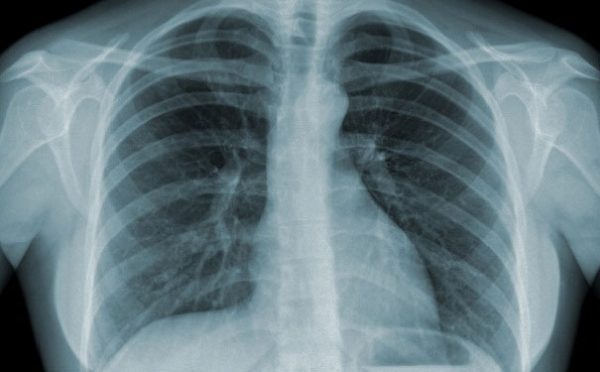

- Chụp X-quang ngực: chụp ảnh phổi, giúp phát hiện các dấu hiệu nhiễm trùng, chẳng hạn như viêm phổi hoặc bất kỳ bệnh nhiễm trùng đường hô hấp trên.